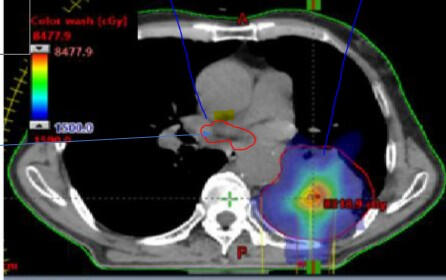

. Phase II Lung Cancer Clinical Trial